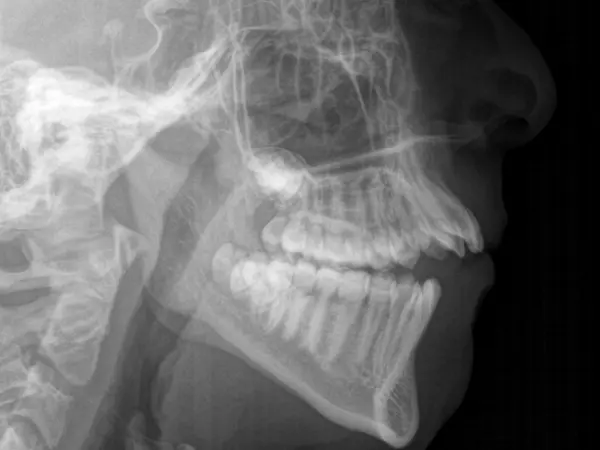

An open bite occurs when the top and bottom rows of teeth don't touch when the mouth is closed. Open bites can occur in the front of the mouth (anterior open bite) or the back (posterior open bite), although front-teeth open bite is more common. Genetics or prolonged thumb-sucking in childhood are common culprits of open bites.

Crossbite, or underbite, is a malocclusion when the top and bottom rows of teeth overlap improperly. The bottom teeth are set past the top teeth when the jaw is closed. This can occur in the front or back teeth, and can create a combination of overbite and underbite, or underbite and open bite.

An overjet is a condition where there's a large horizontal gap between the top and bottom teeth when the mouth is closed. This gap makes the front teeth stick out. This condition is often called "buck teeth." A small overjet is normal, but a larger one requires orthodontic treatment.